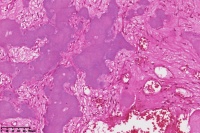

右胫骨内组织,单纯性骨囊肿?

性别

男

年龄

12岁

临床诊断

内生性软骨瘤?骨囊肿?

标本名称

右胫骨内组织

图1